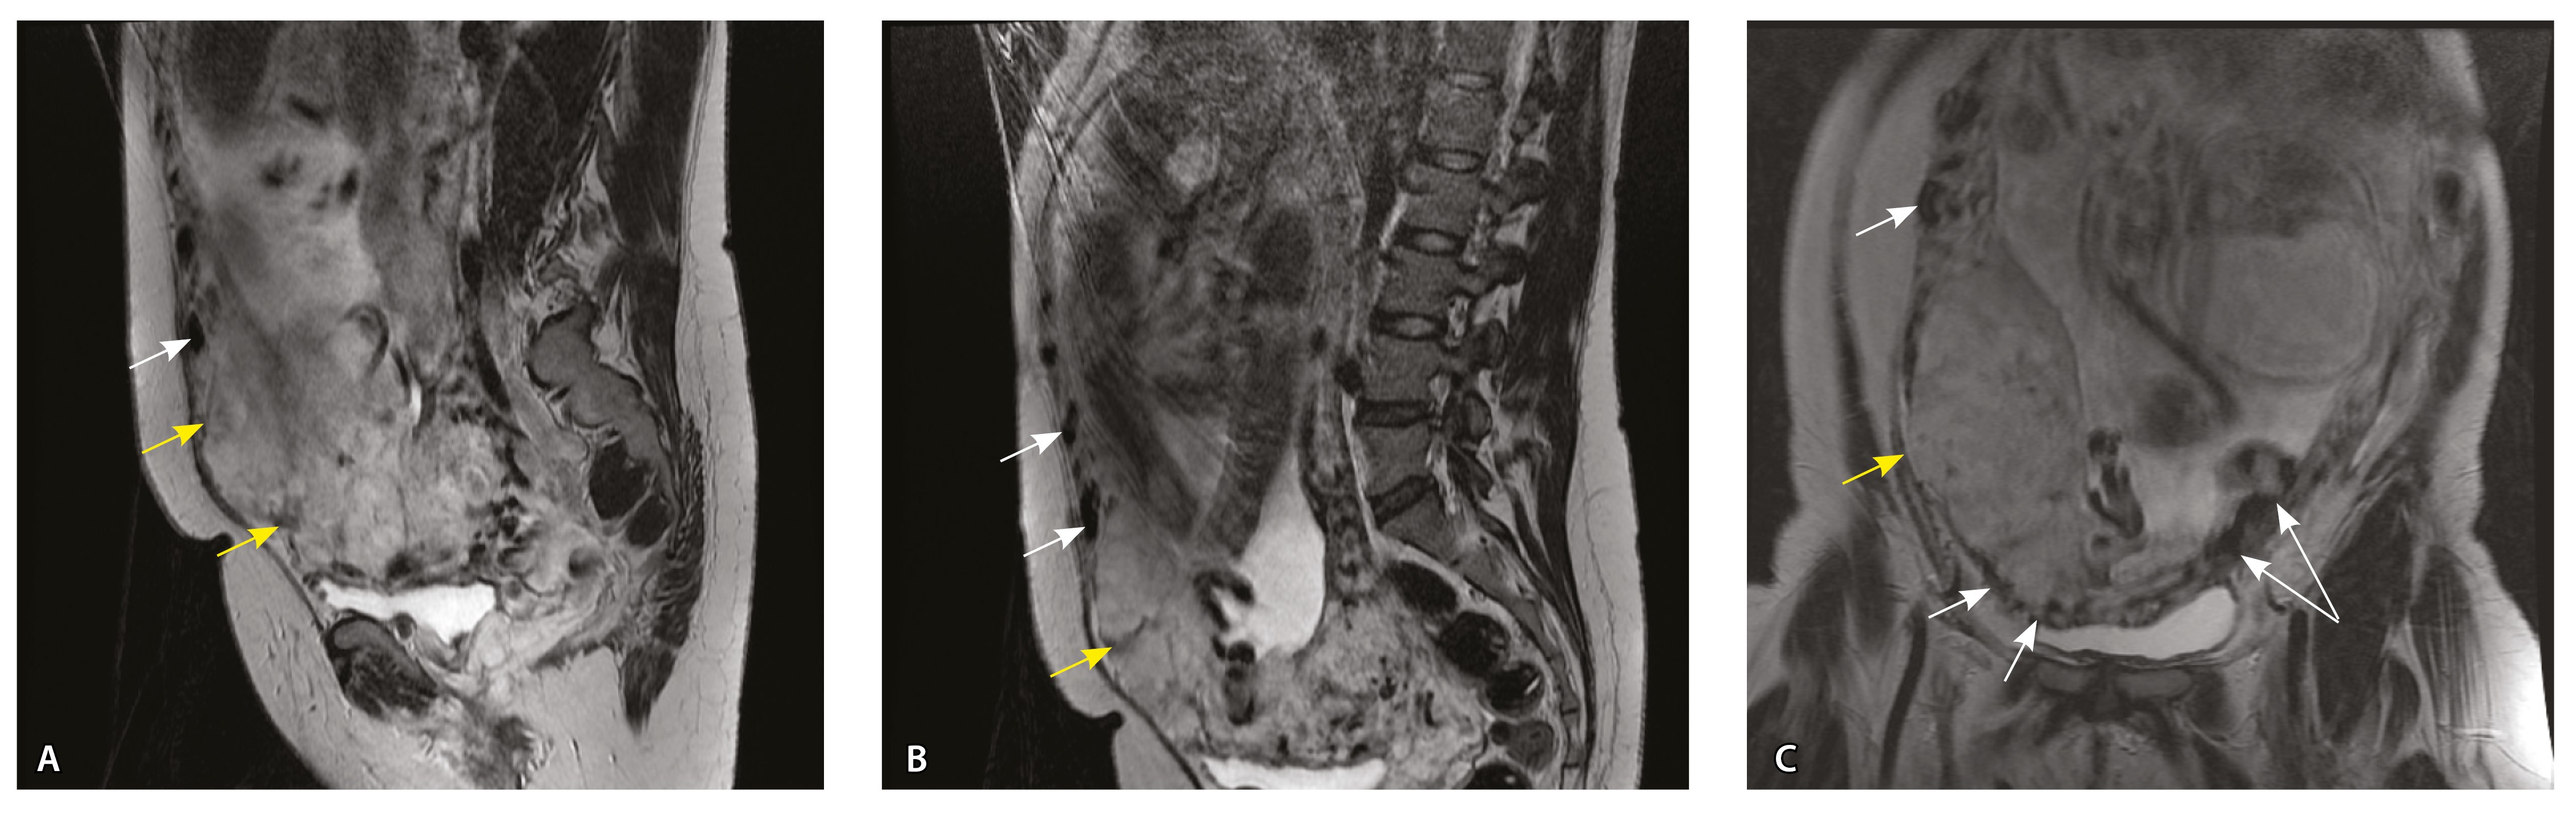

Сосуды 5-го типа. Наличие гиперваскуляризации за пределами матки по данным МРТ, на границе с мочевым пузырем с вовлечением его стенки, сосуды в области перешейка матки, параметрия, в том числе в сочетании с признаками фиброза, наличием рубцово-спаечных изменений и др. Можно предположить, что сосуды 5-го типа являются аналогом pl. рercreta PAS 3b, 3c (рис. 15).

Рис. 15. Беременность 34 недели, pl. percreta, PAS 3b по FIGO (A, Б), PAS 3c по FIGO (В). На магнитно-резонансных томограммах в режиме Т2-взвешенного изображения в сагиттальной (A, В) и аксиальной (Б) плоскостях определяется гиперваскуляризация в области выраженно истонченного нижнего маточного сегмента с распространением сосудов на заднюю стенку мочевого пузыря в области дна (белые стрелки), в область перешейка матки (желтые стрелки)

Данный вариант в патоморфологической картине наиболее сложен для оценки ввиду того, что такие структуры, как параметрий, перешеек матки, стенка мочевого пузыря, обычно не предоставляются в виде макропрепаратов, поэтому визуальные методы, в частности МРТ, могут с большей точностью оценить вовлеченность смежных структур. На микропрепаратах данный вариант инвазии плаценты сочетается с рубцово-спаечными изменениями задней стенки мочевого пузыря с нижним маточным сегментом (рис. 16).

Рис. 16. Гистологическое исследование маточно-плацентарного сегмента при pl. percreta, определенной по данным магнитно-резонансной томографии. Окраска пикрофуксином по Маллори (красный цвет – мышечные волокна, голубой – соединительная ткань). Стенка мочевого пузыря плотно сращена с истонченным маточным сегментом, характеризуется наличием кровеносных сосудов (синяя стрелка). Фиброз задней стенки мочевого пузыря, разобщенные мышечные пучки, замурованные в соединительную ткань (поле отмечено пунктиром). Инвазия ворсин плаценты в бухты миометрия (помечена черным треугольником). Слизистая мочевого пузыря показана стрелкой. Ретроплацентарная гематома помечена звездочкой. Коллаж из 12 фото при увеличении × 100

Как видно на рис. 17, сосуды 5-го типа встречались только при глубокой инвазии плаценты по типу pl. percreta (gr 5) (р < 0,001, хи-квадрат Пирсона).

Сосуды 5-го типа определялись только у пациенток с pl. percreta (77,8%) по данным МРТ (PAS 3b, 3c по FIGO). Визуальная картина была обусловлена наличием гиперваскуляризации по поверхности матки в том числе на границе с мочевым пузырем, перешейком матки и параметрием. Нередко подобные изменения сочетались с признаками фиброза. При патоморфологическом исследовании в этой группе пациенток признаком pl. percreta считался рубцово-спаечный процесс с задней стенкой мочевого пузыря, в том числе в сочетании с сосудами 4-го типа, что было обнаружено всего у 2 пациенток. В то же время в литературе рl. percreta описана как редкое проникновение ворсин за пределы серозной оболочки матки в соседние органы (заднюю стенку мочевого пузыря, перешеек матки, параметрий), подтвержденное патоморфологически, хотя представленные случаи достаточно дискутабельны и не имеют четкого патоморфологического подтверждения [21, 22]. В нашем исследовании не удалось обнаружить ворсины хориона за пределами матки в смежных органах ни в одном из наблюдений. По нашему мнению, истонченный нижний маточный сегмент вместе с различного рода гиперваскуляризацией серозной оболочки матки не может быть единственным достоверным признаком pl. percreta, так как в составе стенки определяется атрофичный миометрий с рубцовой тканью и серозная оболочка матки оказывается неповрежденной. При этом такие структуры, как параметрий, перешеек матки, стенка мочевого пузыря, обычно не предоставляются для исследования в виде макропрепаратов, а в процессе операции удаляется лишь часть стенки матки. Ввиду этого сосуды на наружной поверхности матки лучше визуализируются при инструментальных методах исследования, а не при гистологическом исследовании. В ходе оперативного лечения сосуды могут быть повреждены, также они спадаются, меняется их кровенаполнение, поэтому картина МРТ может существенно отличаться от патоморфологической. Тем не менее проведенный нами анализ сосудов стенки матки показал четкую корреляцию между увеличением диаметра и количества сосудов как в миометрии, так и в составе серозного покрова матки с увеличением степени приращения плаценты. Ряд патоморфологов по-прежнему считает pl. percreta мифом. Но в клинической практике и в практике врачей-рентгенологов на основании МР-признаков данный вариант приращения выделяется и занимает важное место. Для наиболее точной диагностики данные патоморфологического исследования, визуальных методов диагностики, в частности МРТ, интраоперационная картина должны быть оценены не по отдельности, а в совокупности [23].